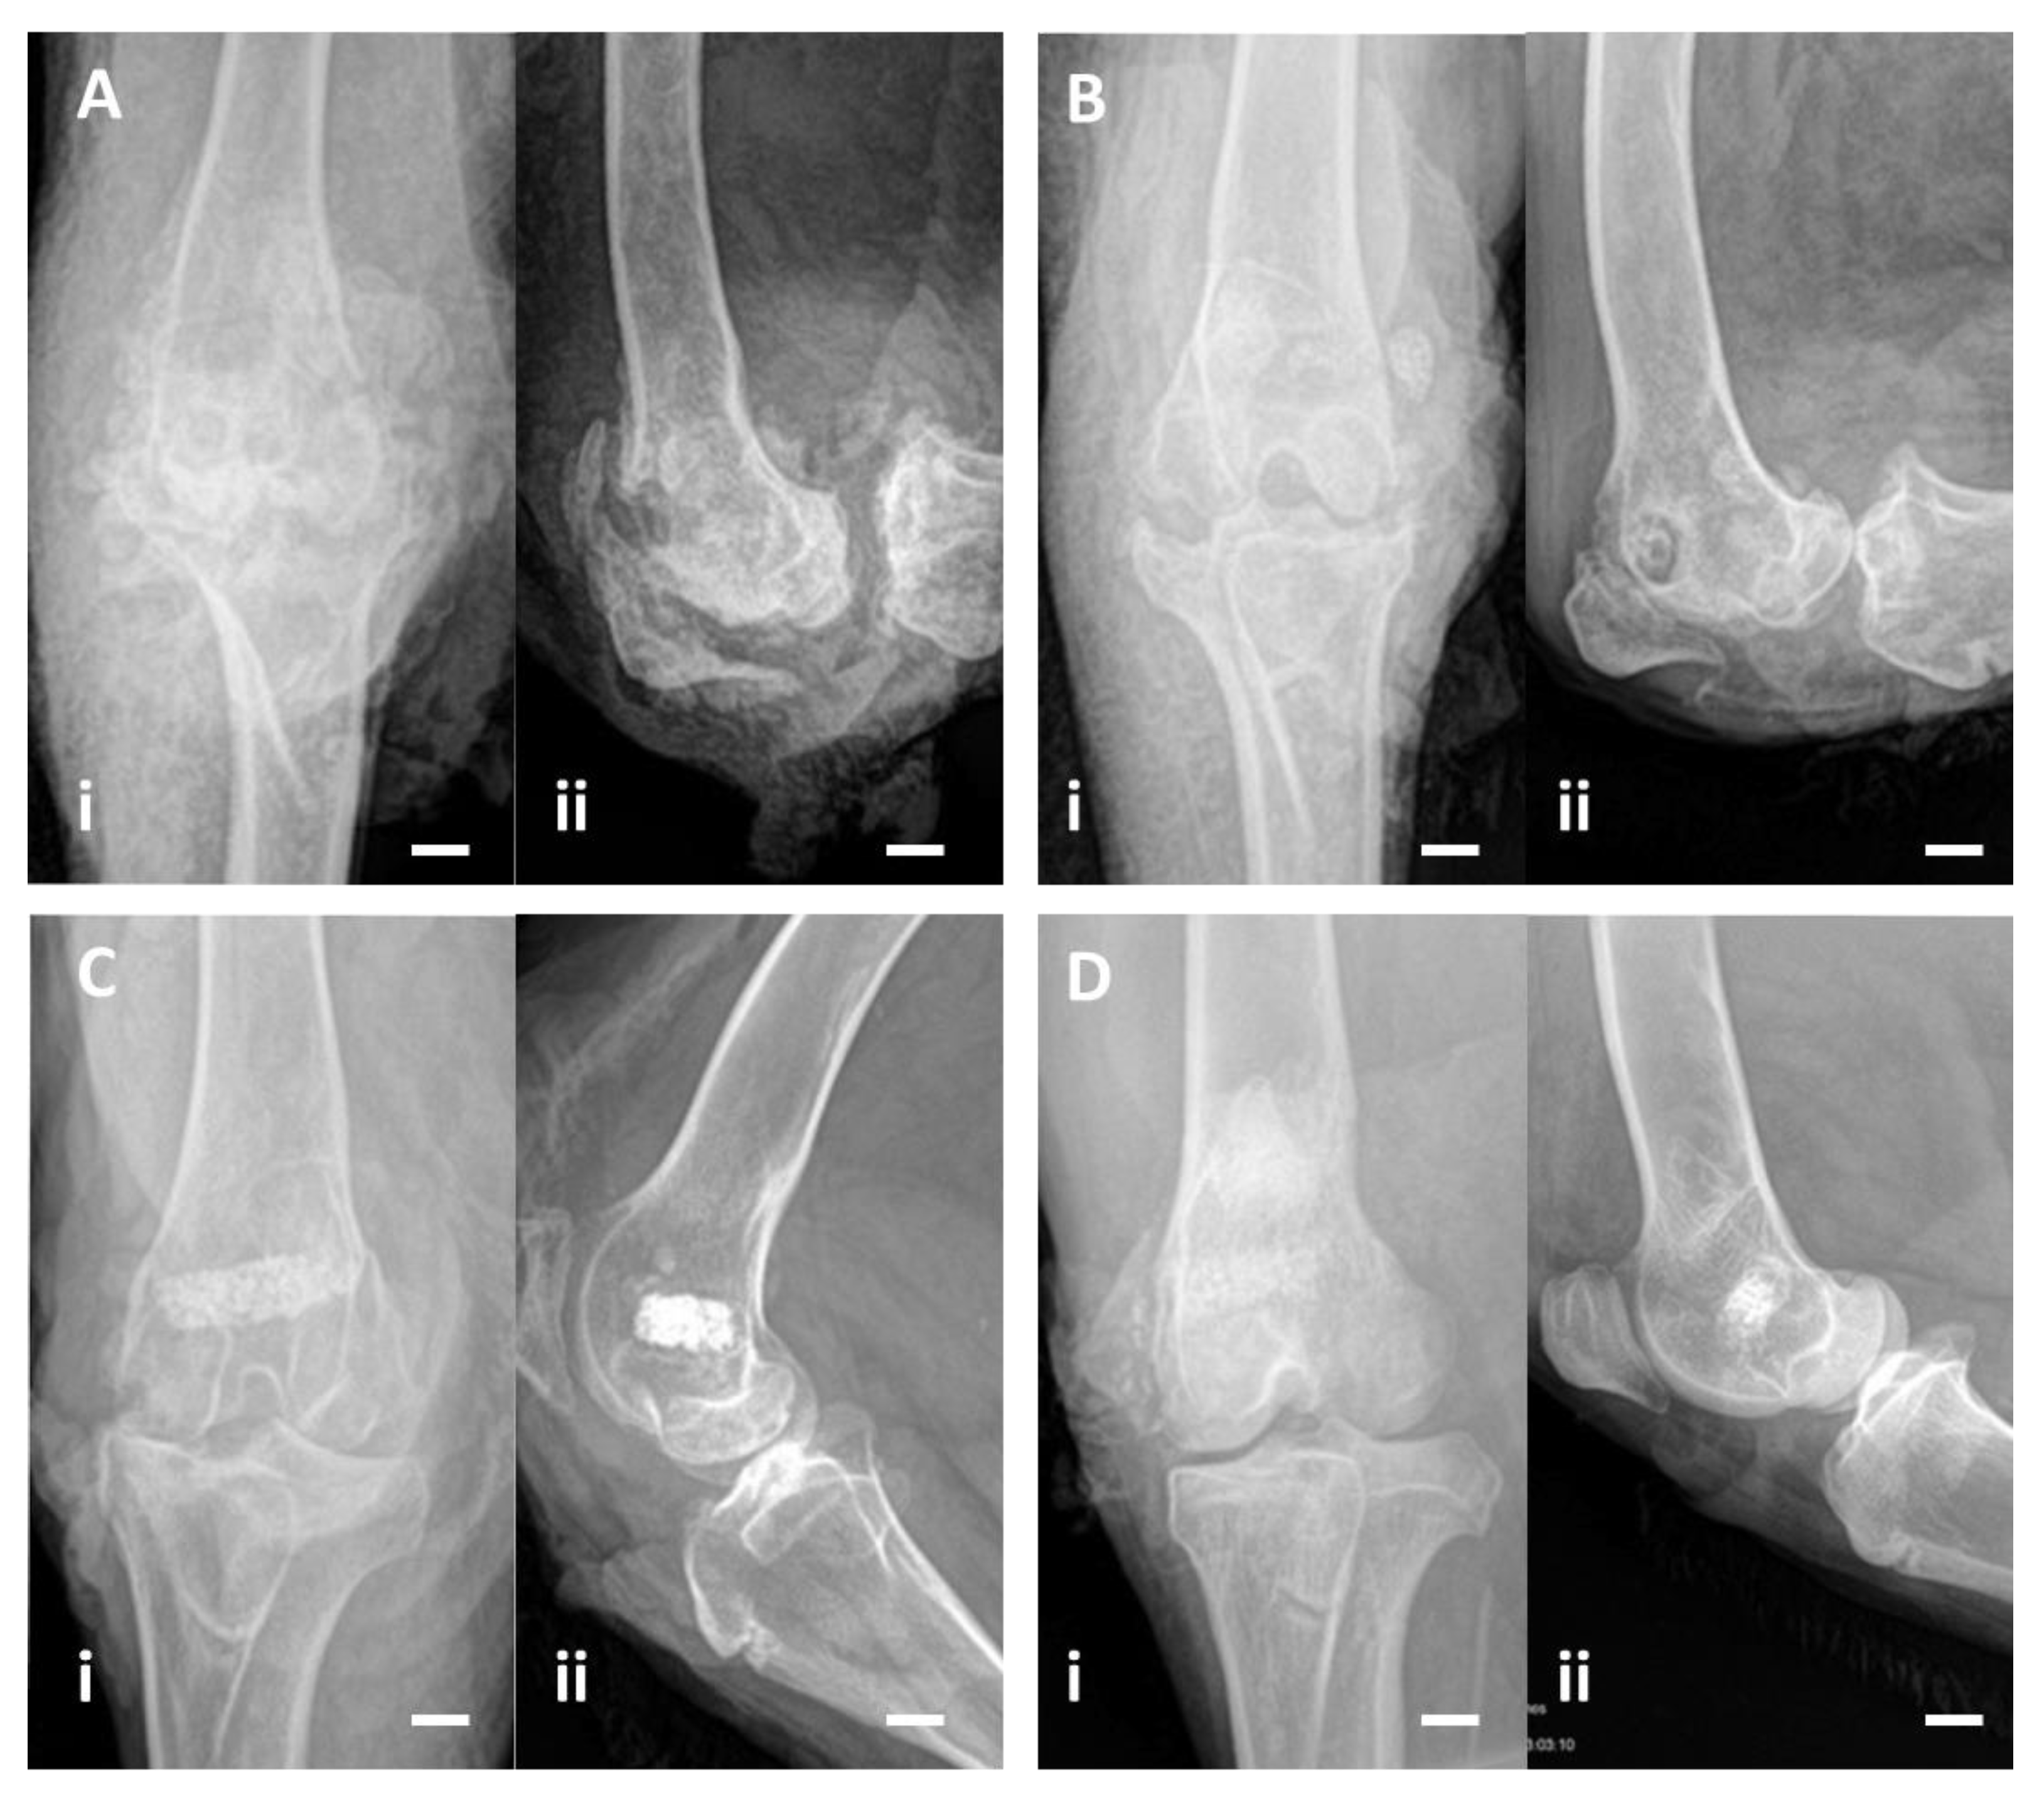

3.2.4. X-rays

| Group | Animal | Rissing Score | Norden Score | ||||

|---|---|---|---|---|---|---|---|

| Initial | At Endpoint | ||||||

| Group A | 1 | 3 | 3 | 4 | 3.33 | 4 | 4 |

| 2 | 3 | 4 | 7 | ||||

| 3 | 3 | 2 | 1 | ||||

| Group B | 4 | 3 | 3 | 4 | 3.67 | 6 | 5.17 |

| 5 | 3 | 4 | 5.5 | ||||

| 6 | 3 | 3 | 4 | ||||

| Group C | 7 | 3 | 3 | 0 | 0 | 0 | 1 |

| 8 | 3 | 0 | 2 | ||||

| 9 | 3 | 0 | 1 | ||||

| Group D | 10 | 0 | 0 | 0 | 0 | 0 | 0 |

| 11 | 0 | 0 | 0 | ||||

| 12 | 0 | 0 | 0 | ||||